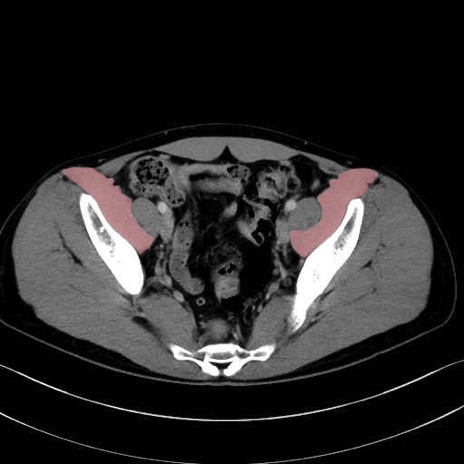

腸骨筋 (Iliacus)